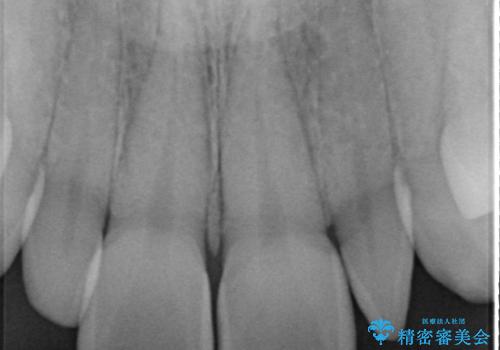

前から2番目の歯が小さく、細くとがった形になっていました。

大きくしようにも、幅が少ない上に、また、内側に入ってしまっているため、矯正治療で前歯を並べてからセラミックでかぶせることにしました。